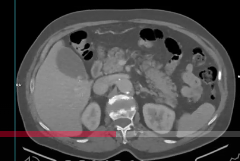

Video 1: reconstrucție în plan axial din achiziție CT abdomen superior în timp venos

Discuţie caz nr 98: La nivelul conținutului colecistului se evidențiază două imagini de calculi rotund-ovalari spontan hiperdensi. Fundic la nivelul peretelui colecistului se evidențiază o leziune rotund-ovalară ce are conținut heterogen tisular și lichidian cu priză de contrast la nivelul porțiunilor tisulare; aspectul este sugestiv pentru adenomioză colecistică.

DE LUAT ACASĂ!!! Calculii colecistici pot fi evidențiați la examinarea CT numai dacă au densități crescute comparativ cu lichidul biliar – trebuie reținut că dacă la examinarea CT nu se evidențiază calculi colecistici nu înseamnă că ei nu există și la acești pacienți se corelează cu examinarea ultrasonografia care detectează 100% calculii biliari. Adenomioza colecistica este o leziune a vezicii biliare, cel mai adesea asociată cu colelitiaza; se caracterizează prin sinusuri Rokitansky-Aschoff înconjurate de fascicule de mușchi netezi hiperplazici.